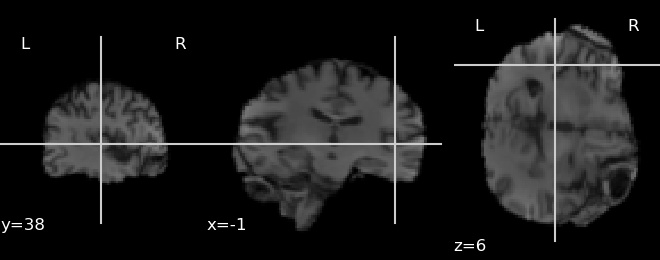

Fig. 1 shows the structure of our preprocessing pipeline. MRI intensity varies from subject to subject. To minimize discrepancies we normalize the values to [0,1]. Then all images were aligned to a standard space named Montreal Neurological Institute (MNI). Then a bias field correction (FAST) [25] is performed to remove general intensity non-uniformities. FNIRT / BET [26] was used to extract brain from the scans removing the skull, fat and background regions which do not contain useful information. The data was registered to MNI152 format (FLIRT) [27, 28]. After that artifact removal was performed, i.e. any voxel intensity values higher than 1 is corrected to be in the range [0,1]. Then a deformation method was applied to extract Gray Matter (GM) and White Matter (WM) from the scan and a 8mm Isotropic Gaussian Kernel was used to smooth and increase the signal-to-noise ratio and remove unnecessary portions of the scan. Finally we have three separate datasets: whole brain scans, GM and WM extracted from the brain and Smoothed GM and WM. An example of the extracted brain and the resultant WM and GM extracted from the brain is given in Fig. 2.

![]() |

| (a) Whole Brain |

| (b) Extracted White Matter |

| (c) Extracted Gray Matter |